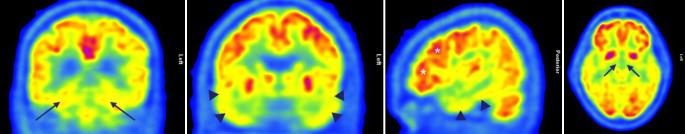

Limbic-predominant age-related TDP-43 (Transactivation response(TAR)-DNA-binding protein 43 kDa) encephalopathy (LATE) has recently been characterized as a distinct neuropathological entity within the spectrum of dementia. Neuropathological alterations in the sense of LATE were already previously described as a comorbidity to Alzheimer's disease (AD) and it has been diagnosed independently from AD pathology in autopsy studies since 2008. The framework of LATE would account for the pathogenetic impact of limbic TDP-43 proteinopathy as a driver of amnestic dementia, either together with comorbid typical AD changes or as a distinct feature. The LATE possibly explains divergent clinical observations and biomarker results in patients suffering from severe amnestic impairment without biomarker evidence of AD-related amyloid and tau alterations. Whether LATE represents a distinct neuropathological entity or is part of the spectrum of neurodegenerative diseases associated with TDP-43 is currently a matter of debate. Further studies on the role of TDP-43 in the development of amnestic dementia are urgently needed. Thus, the enrichment of an amnestic phenotype in amyloid-centered therapeutic drug studies bears the risk of higher rates of patients with TDP-43 comorbidity, which could hinder the proof of efficacy in such trials. This article presents the current state of the discussion on LATE and illustrates the concept and the clinical considerations with a case study.

边缘叶为主的年龄相关性TDP-43(反式激活应答(TAR)-DNA结合蛋白43 kDa)脑病(LATE)最近被确定为痴呆症谱系中的一种独特神经病理学实体。LATE意义上的神经病理学改变先前已被描述为阿尔茨海默病(AD)的一种合并症,自2008年以来在尸检研究中已独立于AD病理学进行诊断。LATE的框架将解释边缘叶TDP-43蛋白病作为遗忘性痴呆驱动因素的致病影响,无论是与典型的AD合并改变一起,还是作为一种独特特征。LATE可能解释了患有严重遗忘性损害但无AD相关淀粉样蛋白和tau改变生物标志物证据的患者的不同临床观察结果和生物标志物结果。LATE是一种独特的神经病理学实体还是与TDP-43相关的神经退行性疾病谱系的一部分,目前仍存在争议。迫切需要进一步研究TDP-43在遗忘性痴呆发展中的作用。因此,以淀粉样蛋白为中心的治疗药物研究中遗忘性表型的富集存在TDP-43合并症患者比例更高的风险,这可能会阻碍此类试验中疗效的证明。本文介绍了关于LATE的当前讨论状态,并通过一个案例研究说明了该概念和临床考虑因素。